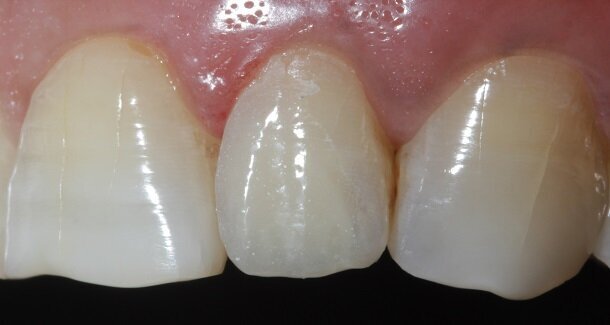

Fig 22, 23 and 24 - In the post-rehydration follow-up appointment, the patient requested us to reduce the lengths of the central incisors slightly, and we reduced it by 0.5mm till he was satisfied.

Line angles can be used to create illusions of the tooth being wider or narrower as needed, especially in diastema closures. For better control, finishing burs can be used in the contra-angled handpiece with the help of a convertor.

One of the biggest advantages of doing direct restorations is that modifications can always be done chairside depending on what the patient wants.

A well polished direct restoration can add a lot of character to a patient's smile, last a good long time and all this, at a fraction of the cost of an indirect restoration. By strictly adhering to finishing and polishing protocols, we can achieve life-like restorations that are not easily discernible to the eye.